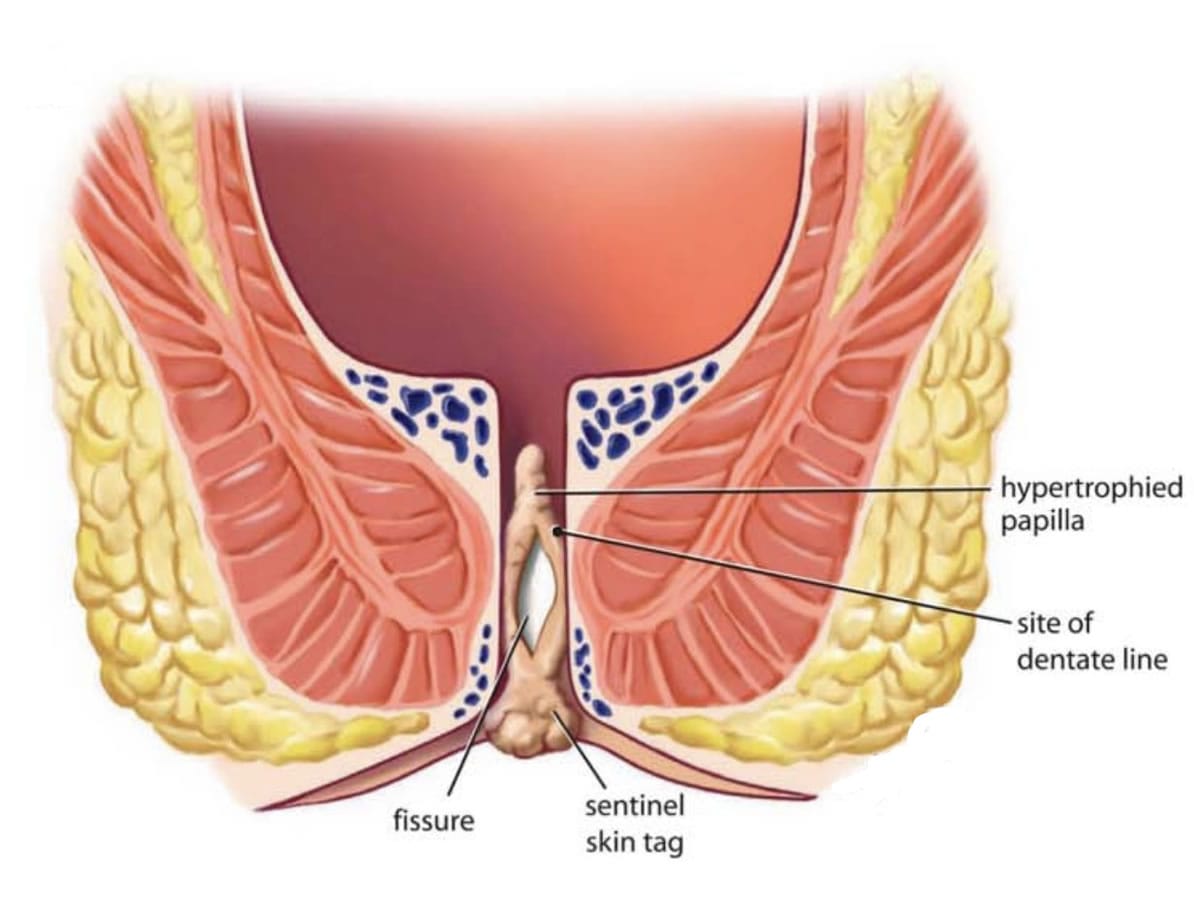

شقاق چیست ؟ چه علائمی دارد؟

شقاق مقعدی به پارگی یا زخم در بافت نازک مقعد اطلاق میشود که میتواند به دلیل عواملی مانند یبوست، زایمان، یا رابطه جنسی ایجاد شود. این مشکل معمولاً با درد شدید، خونریزی، و ناراحتی همراه است. تشخیص صحیح شقاق مقعدی از اهمیت بالایی برخوردار است تا بتوان درمان مناسب را انجام داد.

چگونه میتوان شقاق مقعدی را تشخیص داد؟

تشخیص شقاق مقعدی معمولاً از طریق معاینه فیزیکی توسط پزشک متخصص انجام میشود. پزشک به دنبال علائم ظاهری مانند زخمهای قابل مشاهده، التهاب، و خونریزی خواهد بود. در برخی موارد، ممکن است نیاز به انجام آزمایشهای اضافی باشد تا از وجود مشکلات دیگر مطمئن شویم.

چه علائمی نشاندهنده شقاق مقعدی هستند؟

علائم شقاق مقعدی شامل درد شدید در ناحیه مقعد، خونریزی هنگام دفع مدفوع، و ناراحتی عمومی در ناحیه رکتوم است. این علائم ممکن است در هنگام نشستن یا حرکت نیز تشدید شوند. در صورتی که هر یک از این علائم را تجربه میکنید، درمان خانگی شقاق مقعدی میتواند راهحلی مؤثر باشد.